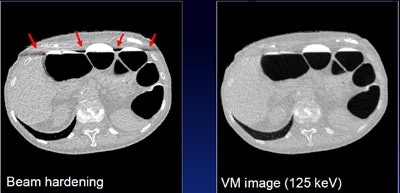

"We're investigating the use of dual-energy CT, which enables material-based detection to better identify the fecal tagging agent and soft-tissue lesions, and also to identify partial-volume fecal tagging artifacts," Nappi said. "Dual-energy CT can be used to synthesize virtual monochromatic images, and these can be used to correct for beam-hardening artifacts due to fecal tagging, and to correct for pseudoenhancement artifacts due to tagging. Ultimately, these will provide quantitatively accurate attenuation for improving the detection accuracy of computer-aided detection."

Nappi and colleagues first calculated material decomposition from the images to identify typical colon materials (air, fat, soft tissue, and fecal tagging), and virtual monochromatic CTC images were reconstructed from the material-decomposition data at 125 keV to minimize image artifacts.